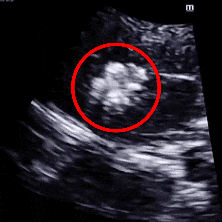

术后6个月复查超声显示:封堵器轮廓模糊,逐渐降解,“三明治”轮廓模糊。TCD发泡试验结果转为阴性,提示右向左分流消失,介入治疗效果显著。

术后6月随访超声

术后6月TCD发泡实验阴性